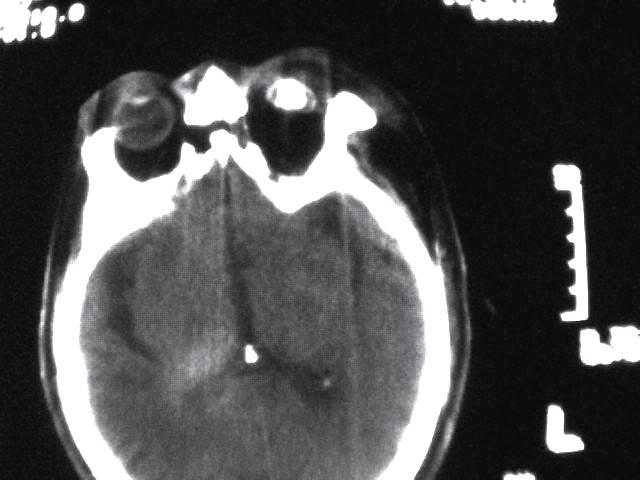

1)考虑为:淋巴瘤或转移瘤。建议:活检。2)左侧眼球痨。